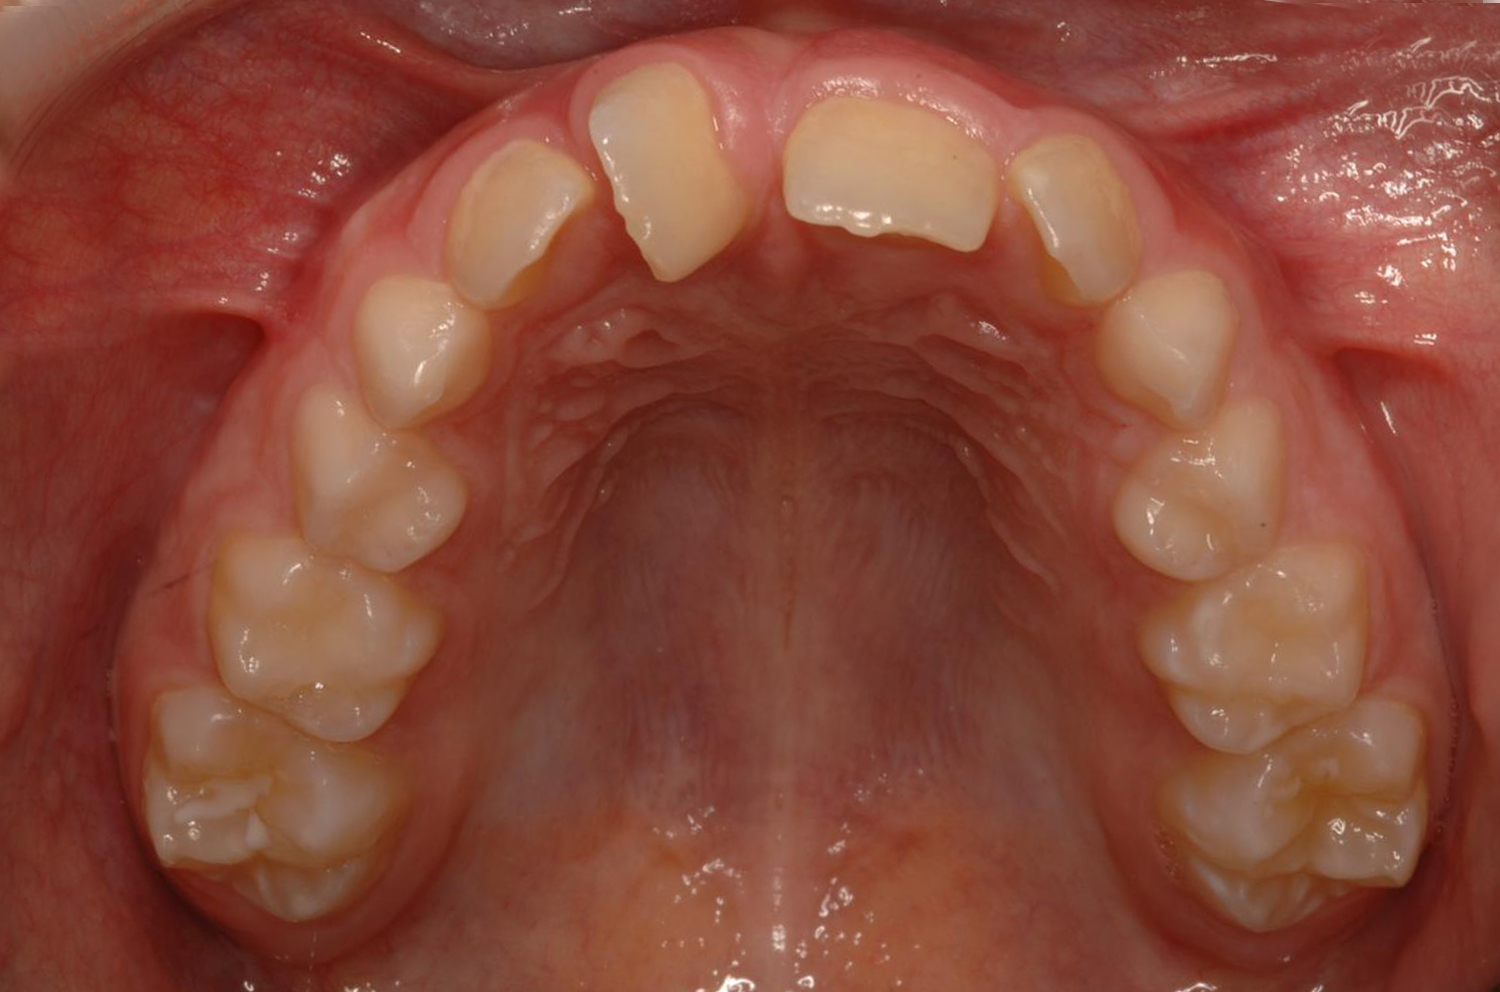

¿Qué son los dientes supernumerarios?

La dentición normal consta de 20 dientes en la dentición de leche y de 32 en la definitiva pero, a veces, nos encontramos con bocas que presentan dientes «extras» o dientes «de más». A éstos, los llamamos dientes supernumerarios. Aparecen en un 2-3% de la población y parece que existe una cierta tendencia hereditaria a presentarlos.

Los dientes supernumerarios son mucho más frecuentes en el maxilar superior que en el inferior. Alrededor del 90% se encuentran curiosamente en la arcada superior.

A veces presentan una anatomía correcta, lo que nos genera la duda de cuál de los dos dientes es el «bueno» y cuál el supernumerario. Otras, la mayoría, suelen ser dientes pequeños, con coronas amorfas y raices cortas.

La ubicación más frecuente de todas es entre los dos dientes centrales superiores. A estos dientes supernumerarios les llamamos «mesiodens». La erupción anormal de alguno de los dos incisivos nos pueden hacer sospechar de la presencia de uno o varios dientes supernumerarios.

Ante la presencia de un diente que ha erupcionado muy descolocado en la arcada, o de dos incisivos centrales superiores con un espacio importante entre sí que no se debe a un frenillo demasiado grueso y bajo, o cuando un diente concreto no termina de erupcionar a pesar de que todos los dientes adyacentes ya lo han hecho, debemos sospechar de la posible presencia de dientes supernumerarios.